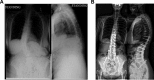

Results: A total of 350 patients were identified: 173 OPEN patients and 177 MIS. OPEN patients were significantly younger than MIS patients (61.5 years vs 63.74 years, P = .013). The OPEN group had significantly more females (87% vs 76%, P = .006), but both groups had similar body mass index. Preoperative lumbar Cobb was significantly higher for the OPEN group (34.2°) than for the MIS group (26.0°, P < .001). The mean preoperative Oswestry Disability Index was significantly higher in the MIS group (44.8 in OPEN patients and 49.8 in MIS patients, P < .011). The preoperative Numerical Rating Scale value for back pain was 7.2 in the OPEN group and 6.8 in the MIS group preoperatively, P = .100.

Conclusions: Patients chosen for MIS for ASD are slightly older and have smaller coronal deformities than those chosen for open techniques, but they did not have a substantially lesser degree of sagittal malalignment. MIS surgery was most frequently utilized for patients with an sagittal vertical axis under 6 cm and a baseline pelvic incidence and lumbar lordosis mismatch under 30°.